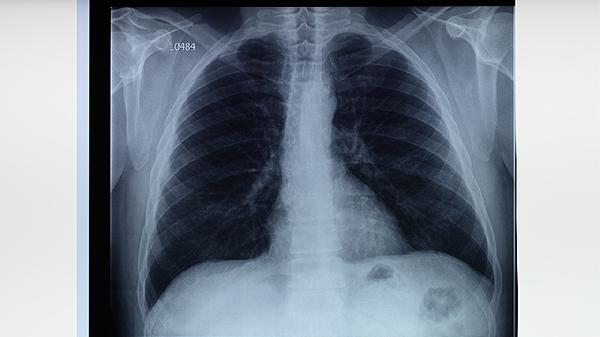

肺結(jié)核主要由結(jié)核分枝桿菌感染引起,發(fā)病原因包括與肺結(jié)核患者密切接觸、免疫力低下、合并慢性疾病、營(yíng)養(yǎng)不良及遺傳易感性等因素。肺結(jié)核通常表現(xiàn)為咳嗽、低熱、盜汗、消瘦等癥狀,可通過(guò)痰涂片檢查、胸部X線等方式確診。

塵肺、慢性阻塞性肺病等肺部基礎(chǔ)病變會(huì)破壞呼吸道防御機(jī)制。此類患者感染結(jié)核菌后易發(fā)展為空洞型肺結(jié)核,表現(xiàn)為咯血、胸痛,需配合鏈霉素注射液與氧療進(jìn)行綜合干預(yù)。

預(yù)防肺結(jié)核需保持室內(nèi)通風(fēng),避免與咳嗽患者密切接觸,規(guī)律作息并保證膳食均衡。高危人群可接種卡介苗,出現(xiàn)咳嗽超過(guò)兩周、痰中帶血等癥狀時(shí)應(yīng)立即進(jìn)行胸部影像學(xué)檢查。治療期間須嚴(yán)格遵醫(yī)囑完成6-9個(gè)月藥物療程,定期復(fù)查肝腎功能,避免擅自停藥導(dǎo)致耐藥性。